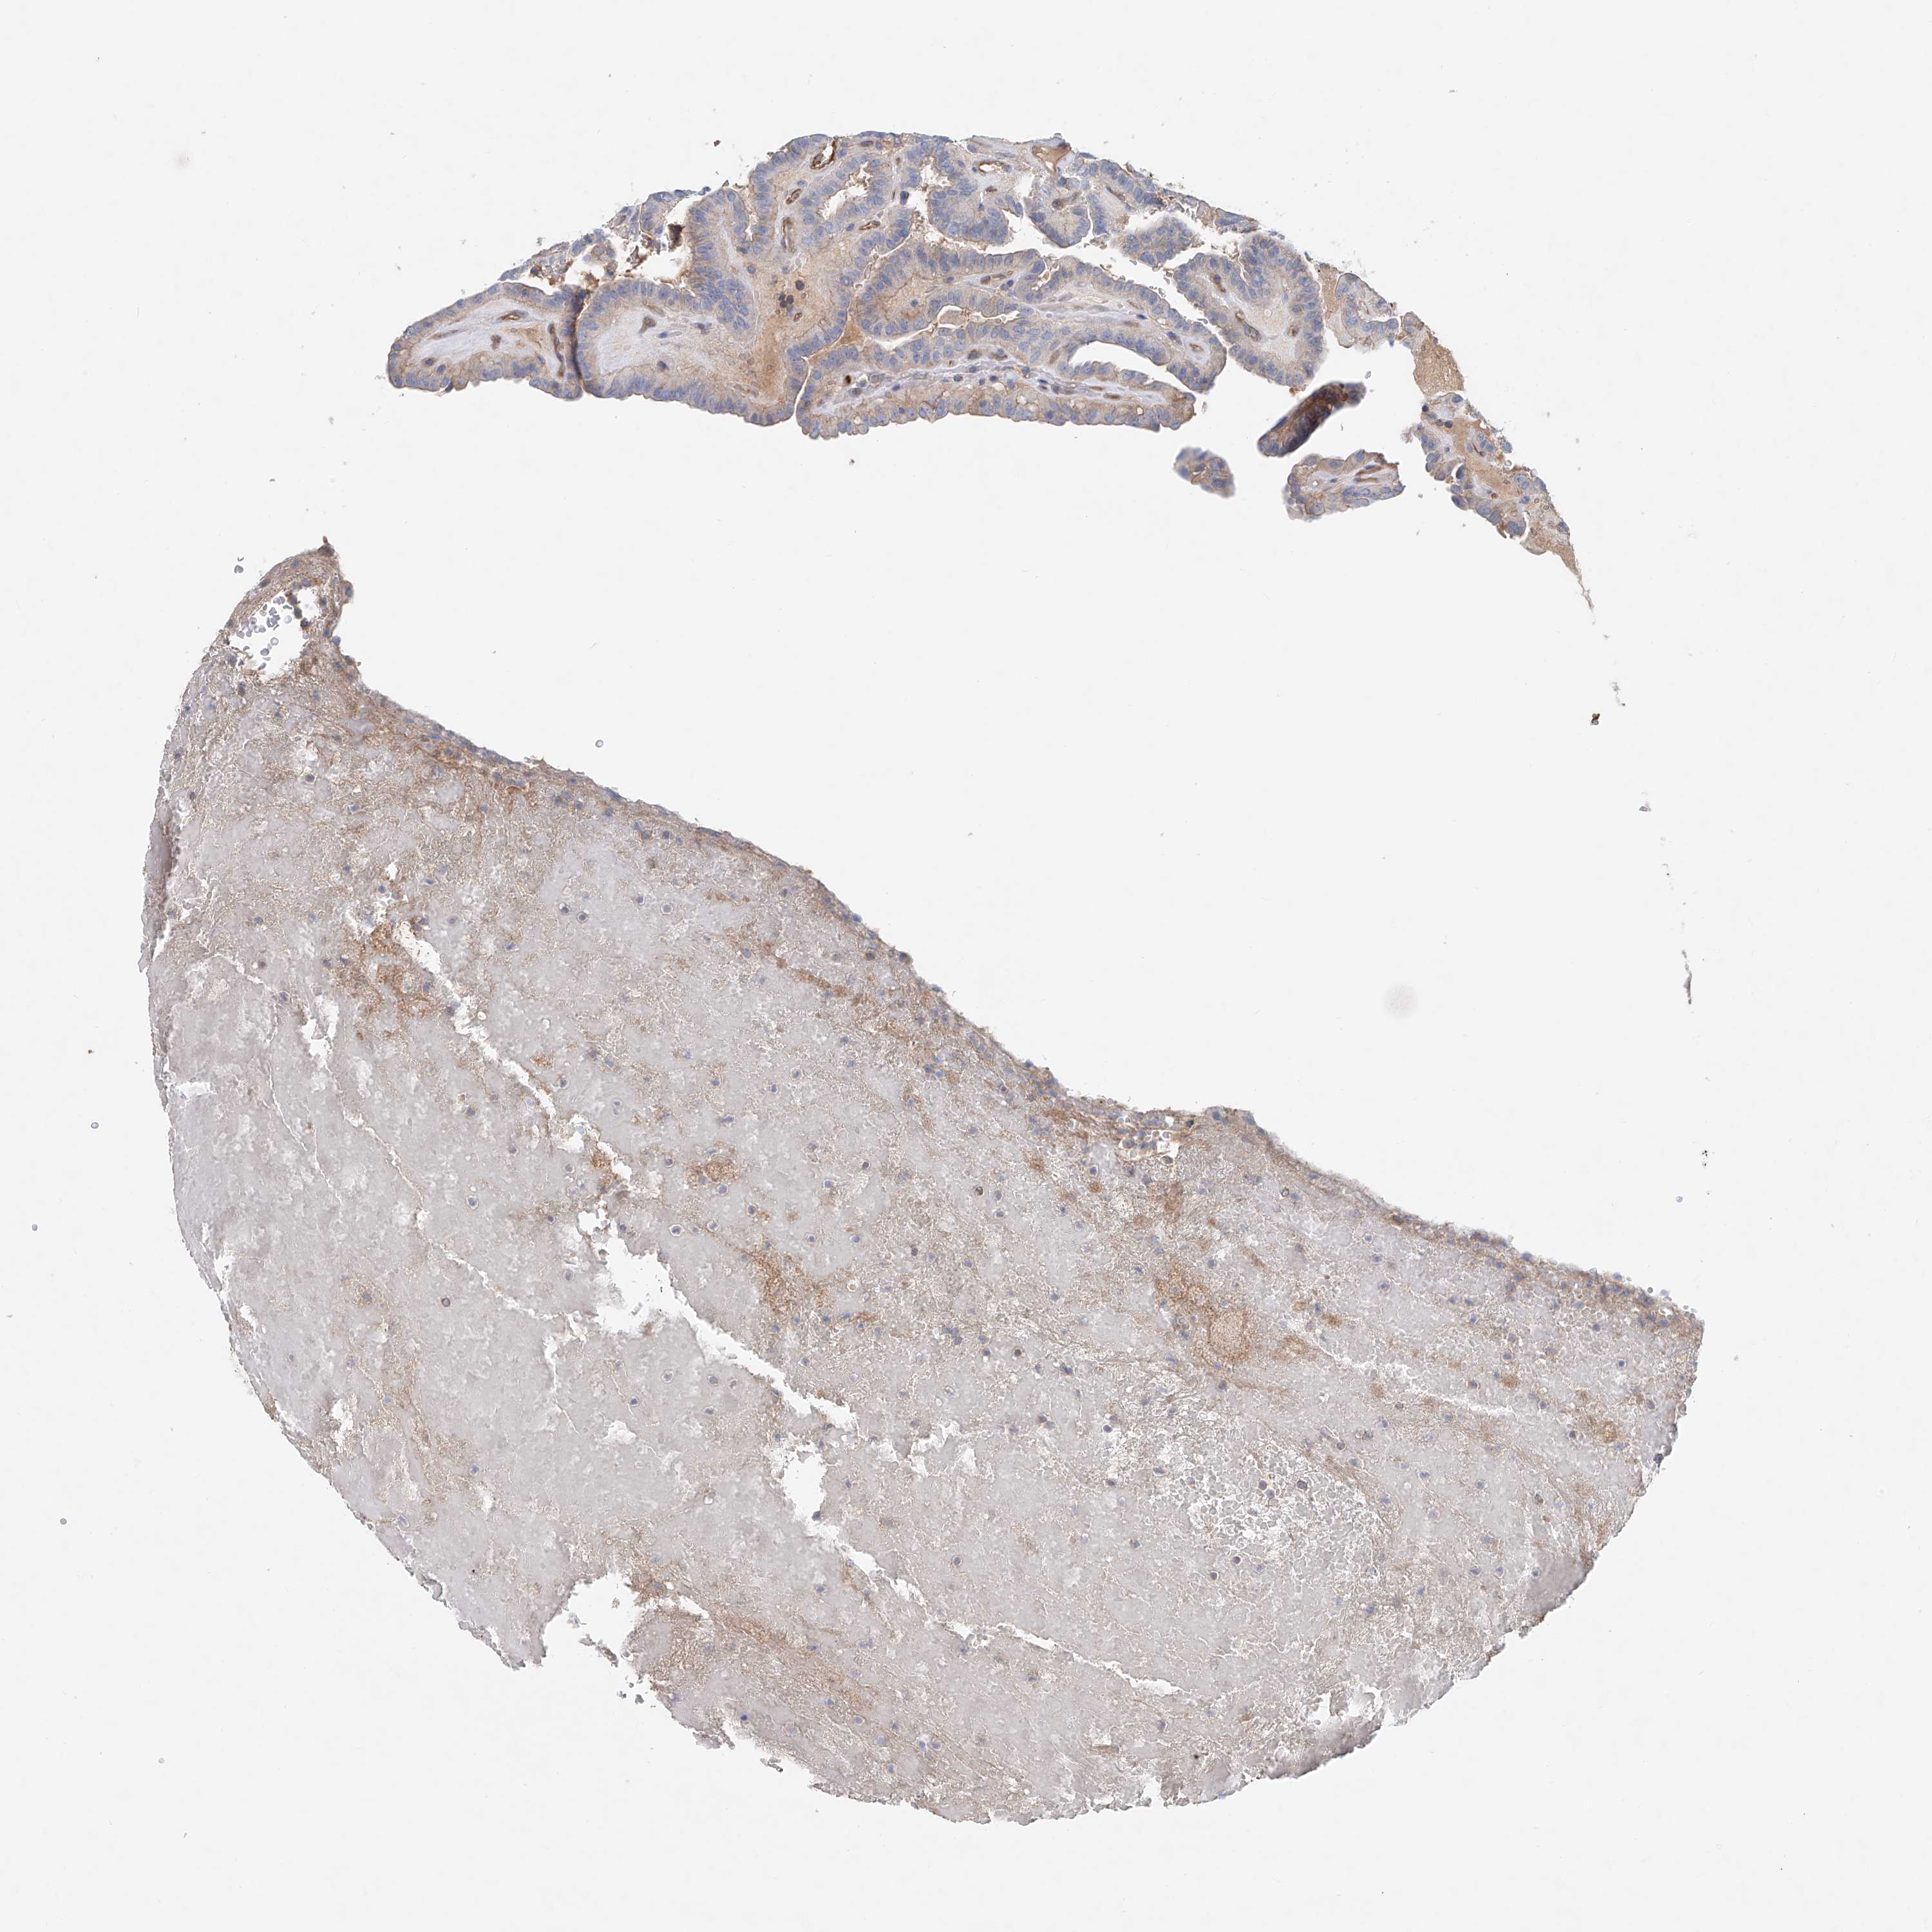

THYROID CANCER - Protein expressioni

A mouse-over function shows sample information and annotation data. Click on an image to view it in a full screen mode. Samples can be filtered based on level of antibody staining by selecting one or several of the following categories: high, medium, low and not detected. The assay and annotation is described here.

Note that samples used for immunohistochemistry by the Human Protein Atlas do not correspond to samples in the TCGA dataset.

Antibody stainingi

Antibody staining in the annotated cell types in the current human tissue is reported as not detected, low, medium, or high, based on conventional immunohistochemistry profiling in selected tissues. This score is based on the combination of the staining intensity and fraction of stained cells.

Each image is clickable and will lead to virtual microscopy that enables deeper exploration of all samples and also displays staining intensity scores, fraction scores and subcellular localization as well as patient and tissue information for each sample.

Antibody HPA031106

Antibody HPA031107

Staining

High

Medium

Low

Not detected

Intensity

Strong

Moderate

Weak

Negative

Quantity

>75%

75%-25%

<25%

None

Location

Nuclear

Cytoplasmic/membranous

Cytoplasmic/membranous,nuclear

Papillary adenocarcinoma, NOS

Follicular adenoma carcinoma, NOS